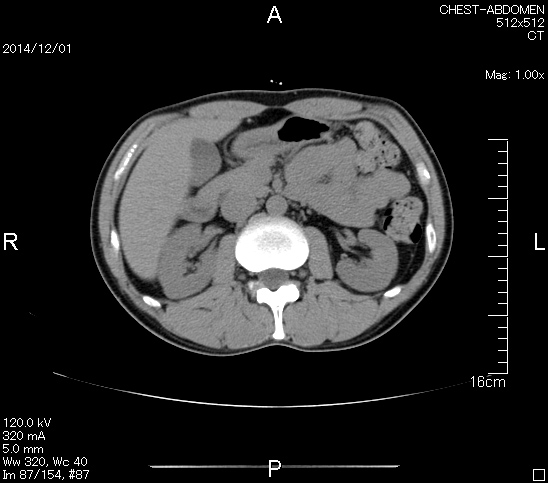

2006年入院治療の退院日から10年。 かなり大きな節目なんだが、なんだろうこの軽い感じは(笑)。 「10年生きたんだぁ」くらい。 変わったような変わっていないような。 当時は10年後なんて全く考えていなかった。 今も10年後は考えていないが・・・。 退院前日の2006/10/31は46.6kgだった。 今日計ったら54.8kg。体脂肪は16.6%。 とても健康にストレスなく生活できていることに、治療当時から現在に至るまで、関わった人全員に感謝の気持ちです。 マーカー、CT画像、問題なし!! 血液検査結果もほとんど文句なしの正常値。 そうだなぁ、数値に出ない異変としては、肩凝りかなぁ。 一旦夏になくなったと思ったが、初秋から再発。 マウスを左手にしたり、シップ貼ったり、最近はホッカイロ貼ったり。 で、一向に良くなる気配がない。 やはり四十肩なのか。 でも肩の可動域は問題ない。動かせないような痛みも無い。 結局色々考えてたどり着いたのは「変形性頚椎症」ではないかと。 肩凝りや頭痛がダラダラと続くようになるという症状がピッタリ当てはまる。 さて、改善策がなかなか難しい。 整形外科行ってもレントゲン撮って湿布をくれるだけだろう。 そんなことに大金を出すならまずは300円/回のプールで泳ごうと思う。 重力から開放して全身運動をするのが一番良いらしい。 2015年の目標は少しでも良いから水泳を再開する、だな。 マーカー、CT画像、問題なし!! 通常の血液検査結果も文句なしの正常値がズラ~っと並んだ!! 間違いなくヨメの食事のおかげである。ほんとうに感謝である!! ちなみに最近少々腰周りの肉付きが気になっていたのだが・・・。 左から2013年12月、2013年06月、2012年12月と背骨の位置は合わせて並べてみた。 6月まではあまり変化がなかったが、この半年で明らかに違う。 背中側の脂肪がやや増えてはいる。 でも最も大きな違いは、腸なのか、やたらと内臓が膨れている・・・。 一言で言うと食べすぎ?!?! 食事は野菜中心ではあるが、確かによく食べているw。 せっかくスーツのウエストを詰めたんだからこれ以上にならないようにしたい。 「腹八分目を心がける」かな。